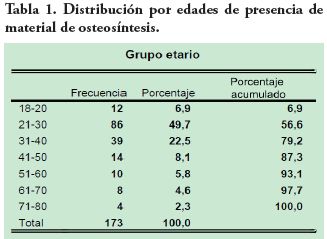

Se encontraron 173 (1,7 %) radiografías con hallazgos sugerentes de la presencia de material de osteosíntesis. La edad media de este grupo de pacientes fue de 33.8 años, 104 (60,1 %) mujeres y 69 (39,9 %) hombres (p=0,5). El grupo entre 21 y 30 años presentó mayor presencia de material con 86 radiografías (48,7 %), mientras que en el grupo entre 71 y 80 años se encontró 2,3 % (4) pacientes; la Tabla 1 resume la distribución por edades de las 173 radiografías.